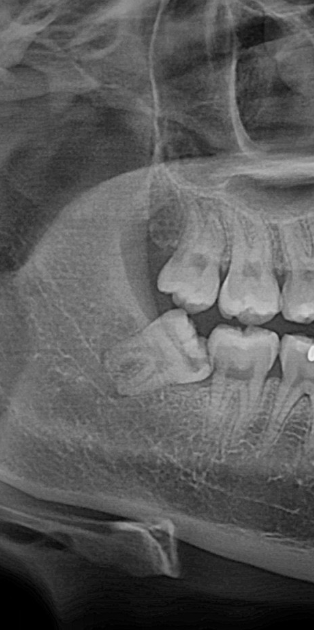

사랑니 4개, 하루에 다 뽑아도 될까요? - 이미지 1

사랑니 4개, 하루에 다 뽑아도 될까요? - 이미지 2

사랑니 4개, 하루에 다 뽑아도 될까요? - 이미지 3

사랑니 4개, 하루에 다 뽑아도 될까요? - 이미지 4

사랑니 4개, 하루에 다 뽑아도 될까요? - 이미지 5